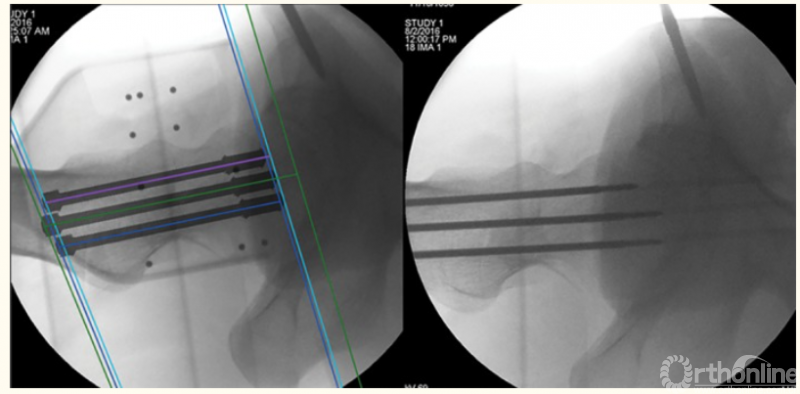

1、肘关节旋转轴三维定位

国内蒋协远教授团队在世界上率先采用三维导航机器人进行肘关节旋转中心定位。TiRobot机器人导航辅助肘关节旋转中心轴定位能够极大地降低主观判断造成的旋转轴偏移,提高轴心定位精准度,减少反复透视验证的过度辐射及反复调整轴心导针的骨质破坏,避免可能的血管、神经损伤,显著减小降低术后肘关节活动阻力,并减少外固定针松动、断裂及外固定架断裂等并发症的发生率,从而整体提高治疗效果。